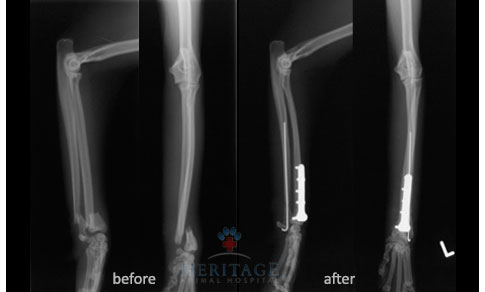

- Fractures — when hit by a car or other accidents